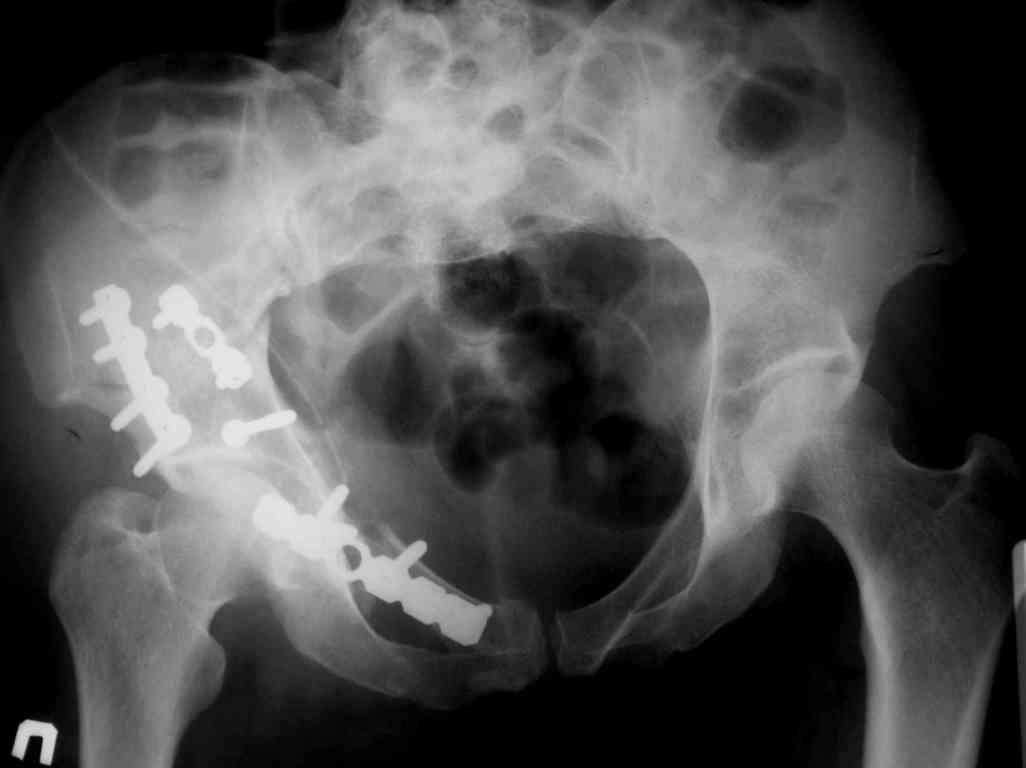

Re: acetabular fracture

У нас есть не большой опыт в лечении подобных больных. Не большой, поскольку к счастью поступают они не часто. Используем подвздошнопаховый доступ хорошо описаный у Мюллера. Манипуляция полностью обработанной ногой на стороне перелома помогает в репозиции и мобилизации сосудов и мышцы вместе с бедренным нервом. Доступ удобный, но требует аккуратности (надо помнить о венах тазового дна). Кроме того до операции делаем 3D реконструкцию. Это позволяет рассмотреть перелом во всей красе и спланировать ход операции.